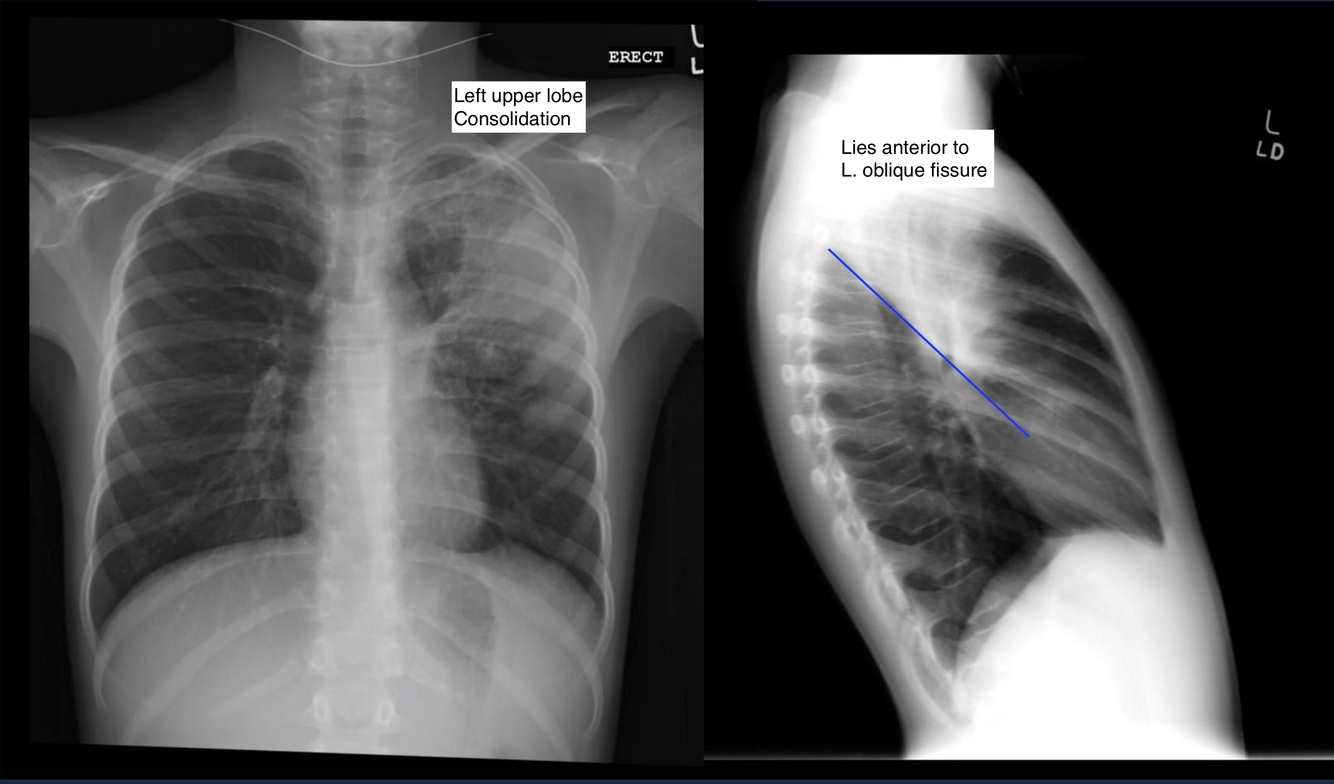

Pneumonia

Infection of the lung with pus in the alveoli or interstitium.